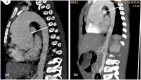

Results: In an 8-year-old boy presenting with severe aortic dilatation, facial dysmorphism, and overgrowth at birth a de novo p.Gly375Arg KCNMA1 mutation was identified which has been reported previously in association with gingival hypertrophy, aortic dilatation, and developmental delay. Additionally, in a 30-week-old fetus with severe growth retardation and duodenal atresia a de novo p.Pro805Leu KCNMA1 mutation was identified. The latter has also been reported before in a boy with severe neurological manifestations, including speech delay, developmental delay, and cerebellar dysfunction.

Conclusion: The current report presents the first antenatal presentation of a pathogenic KCNMA1 mutation and confirms the specific association of the p.Gly375Arg variant with early onset aortic root dilatation, gingival hypertrophy, and neonatal overgrowth.